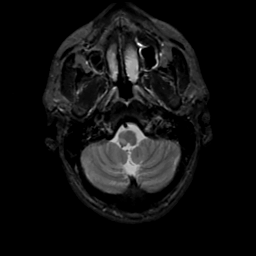

MR Study #8, March 31, 1991 -- Slice #6